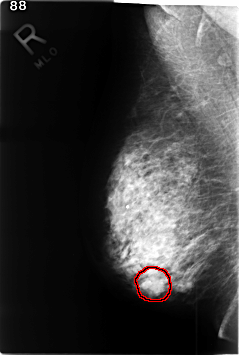

C_0350_1.RIGHT_MLO

FILE: C_0350_1.RIGHT_MLO.OVERLAY

TOTAL_ABNORMALITIES 1

ABNORMALITY 1

LESION_TYPE MASS SHAPE LOBULATED MARGINS ILL_DEFINED

ASSESSMENT 4

SUBTLETY 2

PATHOLOGY MALIGNANT

TOTAL_OUTLINES 1

BOUNDARY